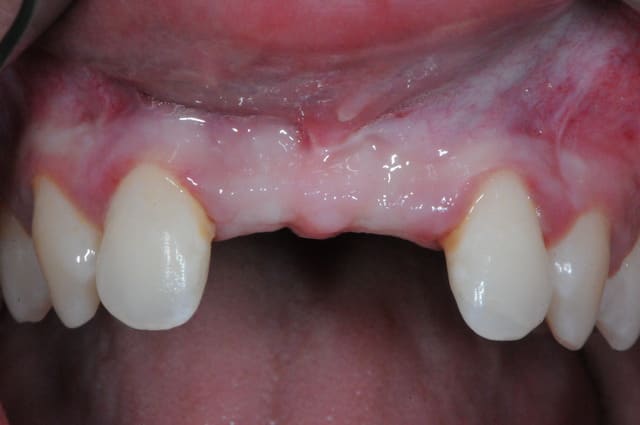

juste pour le plaisir des yeux...

j'étais hier à Strasbourg dans une formation avec Fouad Khoury.

génial ce type!